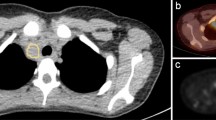

Positron emission tomography (PET) in conjunction with computed tomography is a frequently used modality for staging patients with lymphoma. Utility of PET-computed tomography before or early following auto-SCT has not been as rigorously evaluated. We retrospectively analyzed patients who received auto-SCT for treatment of relapsed or refractory non-Hodgkins lymphoma or Hodgkins disease between the years of 1996 and 2007. Patients who had either a PET scan following salvage chemotherapy within 14 weeks of transplantation (pre-PET), and/or a PET scan 6–14 weeks following transplantation (post-PET) were included. A total of 90 patients were identified for analysis. The median follow-up time is 3.3 years, with a range of 0.13–12.0 years. The median PFS was 4.6 years, and median OS was 5.1 years. At the time of this analysis, 34 patients (37%) experienced disease relapse, and 25 (27%) of the patients died from disease progression. In multivariate Cox proportional hazards analysis, post-PET did not predict for outcome, pre-PET positivity predicted for decrease in PFS. In conclusion, post-PET scan did not predict for PFS or OS in multivariate analysis. Positive pre-PET scan did predict for PFS as seen in previous studies, and may help identify patients who would benefit from innovative post transplant therapies.

Palmer, J., Goggins, T., Broadwater, G. et al. Early post transplant (F-18) 2-fluoro-2-deoxyglucose positron emission tomography does not predict outcome for patients undergoing auto-SCT in non-Hodgkin and Hodgkin lymphoma. Bone Marrow Transplant 46, 847–851 (2011). https://doi.org/10.1038/bmt.2010.203